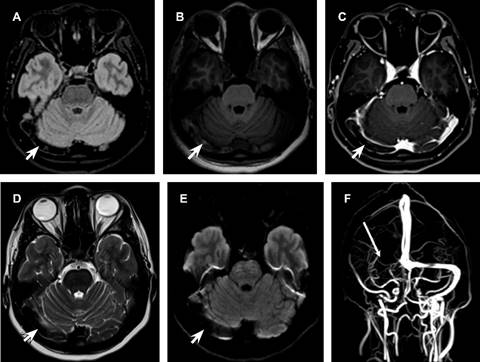

Una mujer de 27 años, con antecedentes de síndrome de ovario poliquístico y tratamiento con drosperinona/etinilestradiol, presentó cefalea punzante en la región temporal derecha irradiada hacia la órbita derecha, fotofobia y algiacusia. La tomografía y resonancia magnética demostraron falta de permeabilidad del sistema venoso del seno transverso, seno sigmoideo, golfos de la yugular derecha e hiperintensidad de los senos longitudinal superior, longitudinal inferior, vena de galeno, seno transverso, seno sigmoideo y golfo yugular en el lado izquierdo, relacionados con enlentecimiento del flujo (Figura 2). Se indicó manejo con enoxoparina y posteriormente rivaroxavan 20 mg/día, presentando mejoría clínica.

Figura 2: RM del encéfalo obtenida con un resonador magnético superconductor de 3T, secuencias: A) FLAIR, B) T1, C) T1 con contraste, D) T2 y E) Difusión, que muestran falta de permeabilidad del seno transverso derecho, presencia de material trombótico y defecto de repleción (puntas de flechas). F) Venorresonancia que muestra falta de permeabilidad del seno trasverso (flecha larga), golfo yugular y vena yugular interna.

La neurorradiología juega un papel vital en la identificación y tratamiento de la TVC. La RM con venografía, una técnica no invasiva, ofrece una visualización detallada de los vasos cerebrales y el parénquima cerebral asociado. En el caso clínico, la RM reveló falta de permeabilidad en varios senos venosos cerebrales e hiperintensidad en otros, lo que facilitó el diagnóstico y tratamiento temprano.